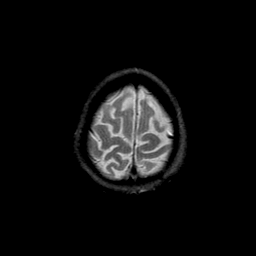

Basal Ganglia Calcification: T2-weighted MR -- Slice #16

[Home][Help][Clinical] Slice 16